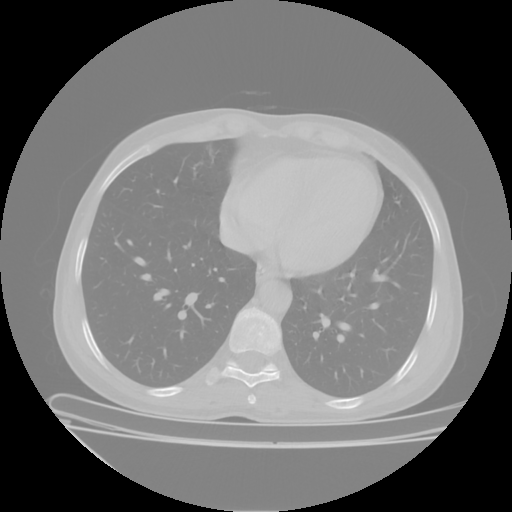

Reconstructed NATIVE CT scan (cycle consistency)

No window - Raw intensity values

Lung window (WL -600, WW 1500 β†’ Low βˆ’1350, High +150)

Mediastinum window (WL 40, WW 400 β†’ Low βˆ’160, High +240)

Targeted Slice 70 - HU-Space Analysis (Generated vs Real Venous)

0.857

HU SSIM

110.8

HU RMSE

52.9

HU MAE

Average HU-Space Metrics Across All Slices (38 slices) - Generated vs Real Venous

0.856

HU SSIM (Avg)

114.8

HU RMSE (Avg)

52.6

HU MAE (Avg)